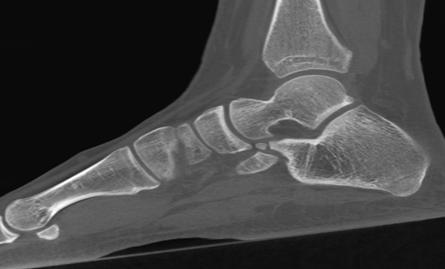

A 16-year-old female, who had presented with repeated left ankle sprains over several years, was consulted at our emergency room for a new left ankle sprain. Radiological evaluation (X-ray and MRI) revealed a discrete oedema of the calcaneal rostrum, with a 4-mm bone fragment between the calcaneum and the navicular bone, making clinicians suspect an avulsion fracture. The talonavicular, spring and bifurcated ligaments were normal. A complementary computed tomography (CT) scan confirmed a 2.8 x 4.5-mm bone fragment with a partially cortical appearance (Figure 1). Treatment was a plaster splint for four weeks. Despite physiotherapy, pain and limited mobility continued, and the patient described pain when walking on non-flat surfaces. On palpation, there was elective pain on the anterolateral side of the mid foot and subtalar motion was restricted. Clinicians proposed a surgical exploration using a lateral approach. We noted synchondrosis/synfibrosis between the calcaneal body and the anterior calcaneal process and between an OCS and the navicular bone. A surgical excision of the OCS was performed, and the extensor digitorum brevis muscle was interposed in the gap left by the removal of the bony piece. At nine months, the patient was walking without pain, had no further sprains and her subtalar motion was no longer restricted.

Figure 1: Computed tomography scan image of a partially cortical bone fragment located between the calcaneus and the navicular bone.

A 13-year-old female presented with chronic pain around her right ankle, with many lateral right ankle sprains over the previous three years. Pain was located at the right ankle’s anterolateral aspect, with palpable mass there, and she reported tenderness on palpation of the anterior aspect of the sinus tarsi and around the dorsolateral aspect of the talonavicular joint. Subtalar motion was severely restricted, without hind foot valgus or flat foot deformity. An ossified structure distinct from the distal end of the calcaneus was visible on lateral foot X-ray. Using the 45° oblique view, this bone formation was on top of the anterior process of the calcaneus, superimposed on the calcaneocuboid joint. A CT scan showed a large accessory ossicle (20x12x8mm) attached to the anterior calcaneal facet by a fibro cartilaginous union resembling a synchondrosis. This ossicle was in a space between the anterior aspect of the calcaneus and the navicular bone. Conservative therapy (immobilization with a cast and physiotherapy) was unsuccessful. Surgical treatment consisted of excising this accessory ossicle. After three years of follow-up, the patient was pain-free and her subtalar motion was no longer restricted.